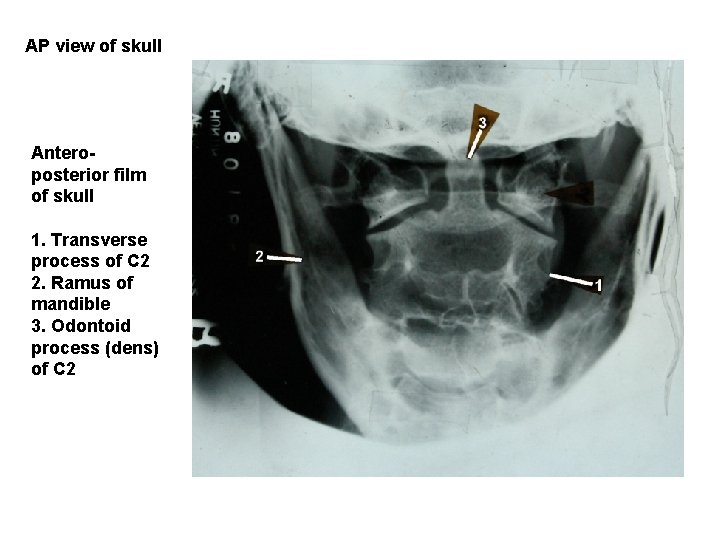

AP view of skull Anteroposterior film of skull 1. Transverse process of C 2 2. Ramus of mandible 3. Odontoid process (dens) of C 2